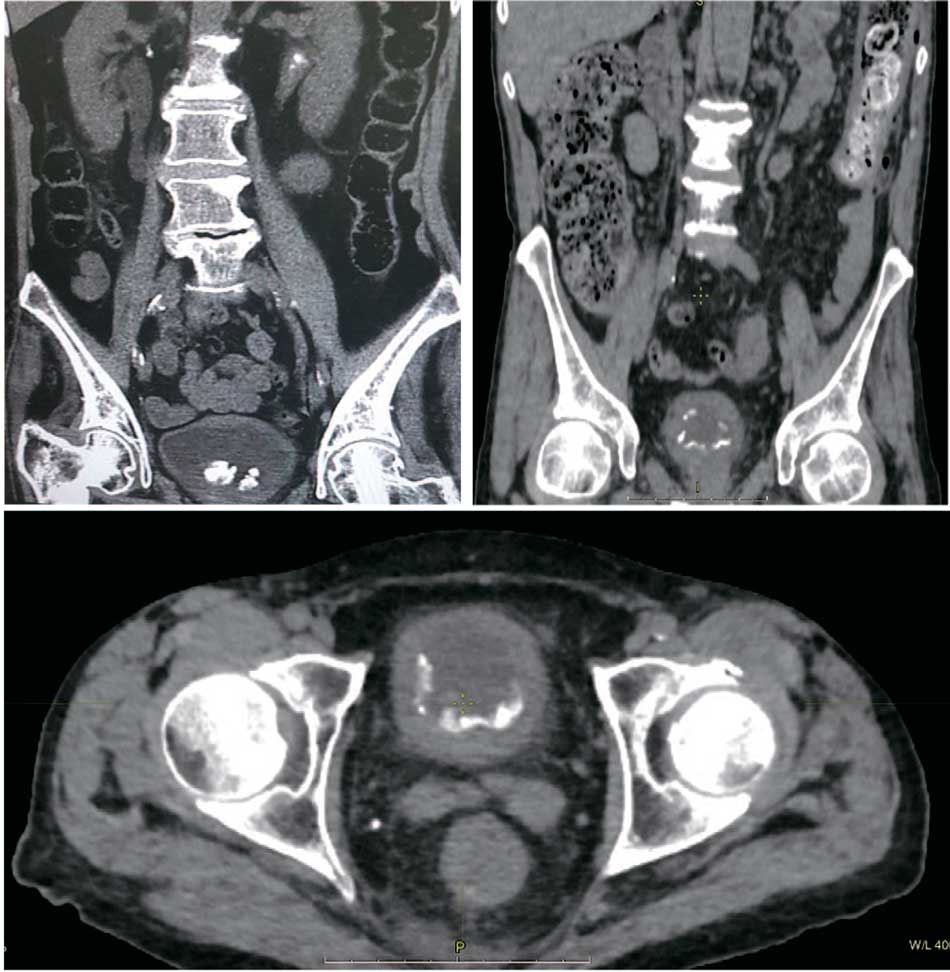

По данным КТ органов малого таза у всех пациентов выявлено утолщение стенки наполненного мочевого пузыря свыше 4 мм, инкрустация слизистой на различных по площади участках; наличие конкрементов в просвете мочевого пузыря, как фиксированных, так и свободно лежащих (рис. 2).

Рис. 2. Компьютерная томография. Картина конкрементов в просвете мочевого пузыря при инкрустирующем цистите

Fig. 2. Computed tomography. The picture of concretions in the lumen of the bladder with encrusting cystitis